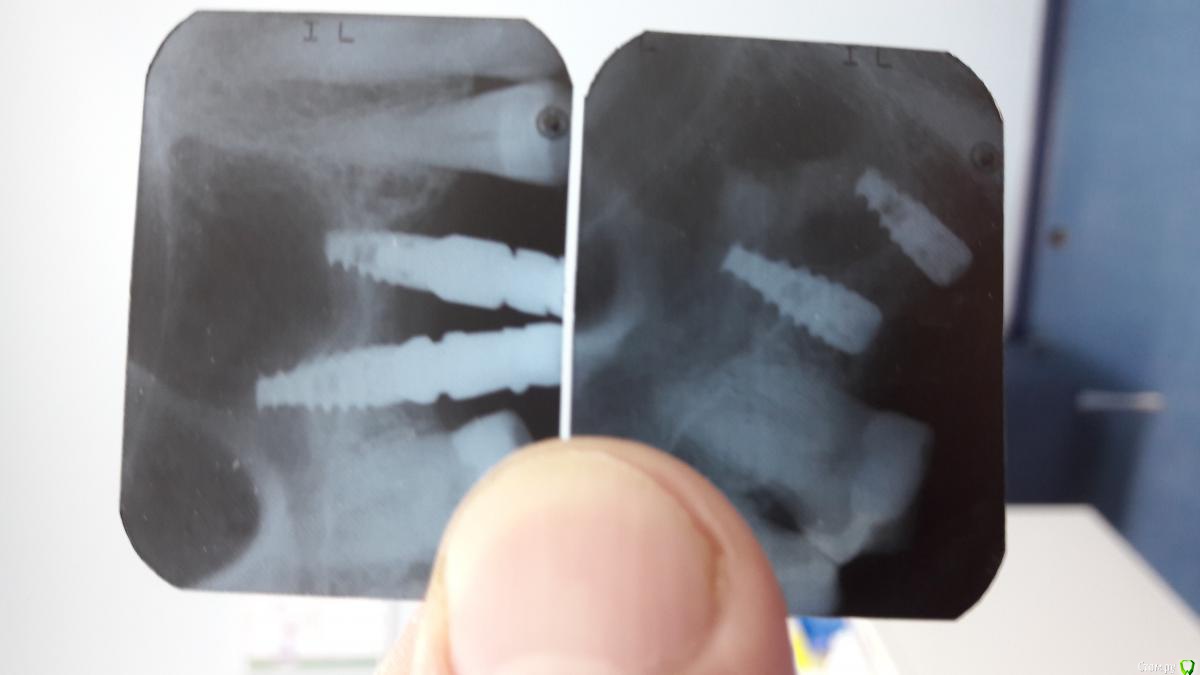

AlexanderGudkov Опубликовано 11 октября, 2016 Автор Поделиться Опубликовано 11 октября, 2016 Год прошел) http://s017.radikal.ru/i409/1610/cf/bdf843a4ca90.png http://s019.radikal.ru/i623/1610/67/1c3fb9a3b910.jpg 10 Ссылка на комментарий